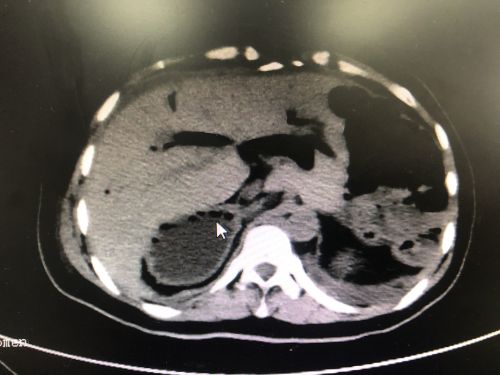

ct显示患者有多个脾脏。(红圈内)

入院后的CT检查发现,张女士不仅有“肝胆管结石并胆管炎”,而且脾脏分裂成4个;不仅如此,4个脾脏和胃、十二指肠都长反了位置——本应在腹腔左侧的脾脏和胃跑到右边,而原本应该在右侧的十二指肠则跑到了左边。